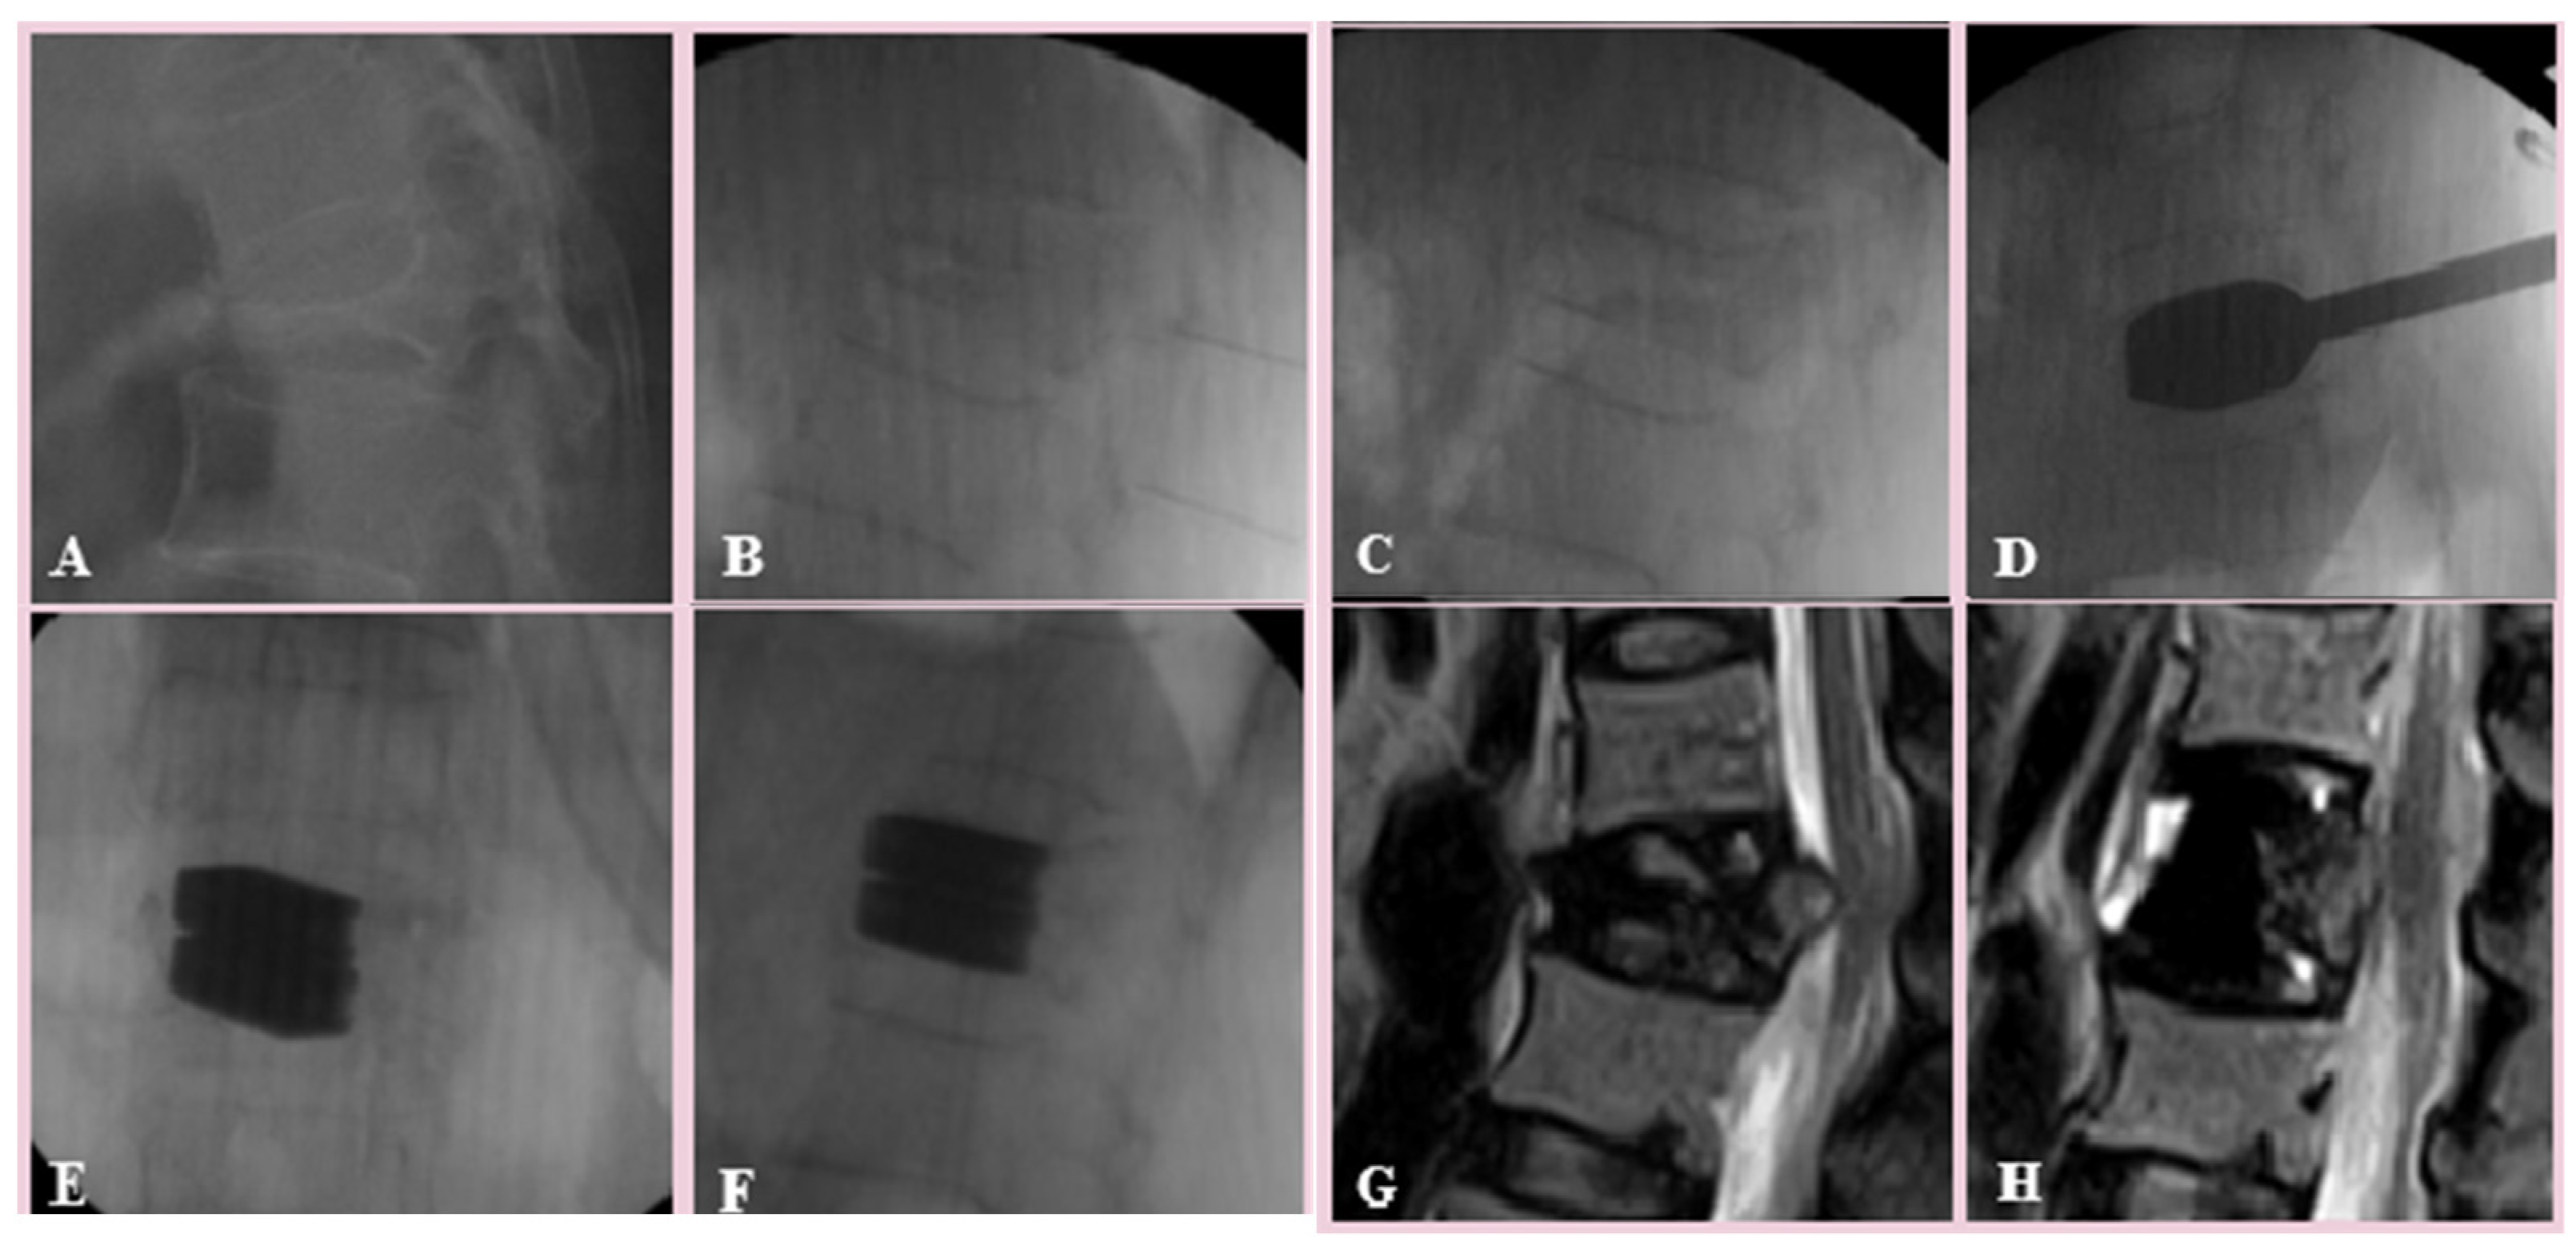

2. Materials and Methods

3. Results

4. Discussion